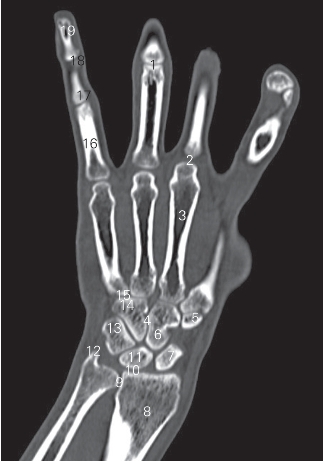

图4-41 经尺骨茎突的冠状断层CT图像(骨窗)

1 近侧指间关节 proximal inter phalangeal joint

2 掌指关节 metacarpophalangeal joint 3 第3掌骨 3rd metacarpal bone

4 腕骨间关节 intercarpal joint 5 小多角骨 trapezoid bone

6 头状骨 capitate bone 7 舟骨 scaphoid bone

8 桡骨 radius

9 远侧尺桡关节 distal radioulnar joint

10 腕关节 carpal joint 11 月骨 lunate bone

12 尺骨茎突 processus styloideus ulnae 13 三角骨 triquetral bone

14 钩骨 hamate bone 15 腕掌关节 carpometacarpal joint

16 近节指骨 proximal phalanx 17 中节指骨 middle phalanx

18 远侧指间关节 distal interphalangeal joint

19 远节指骨 distal phalanx